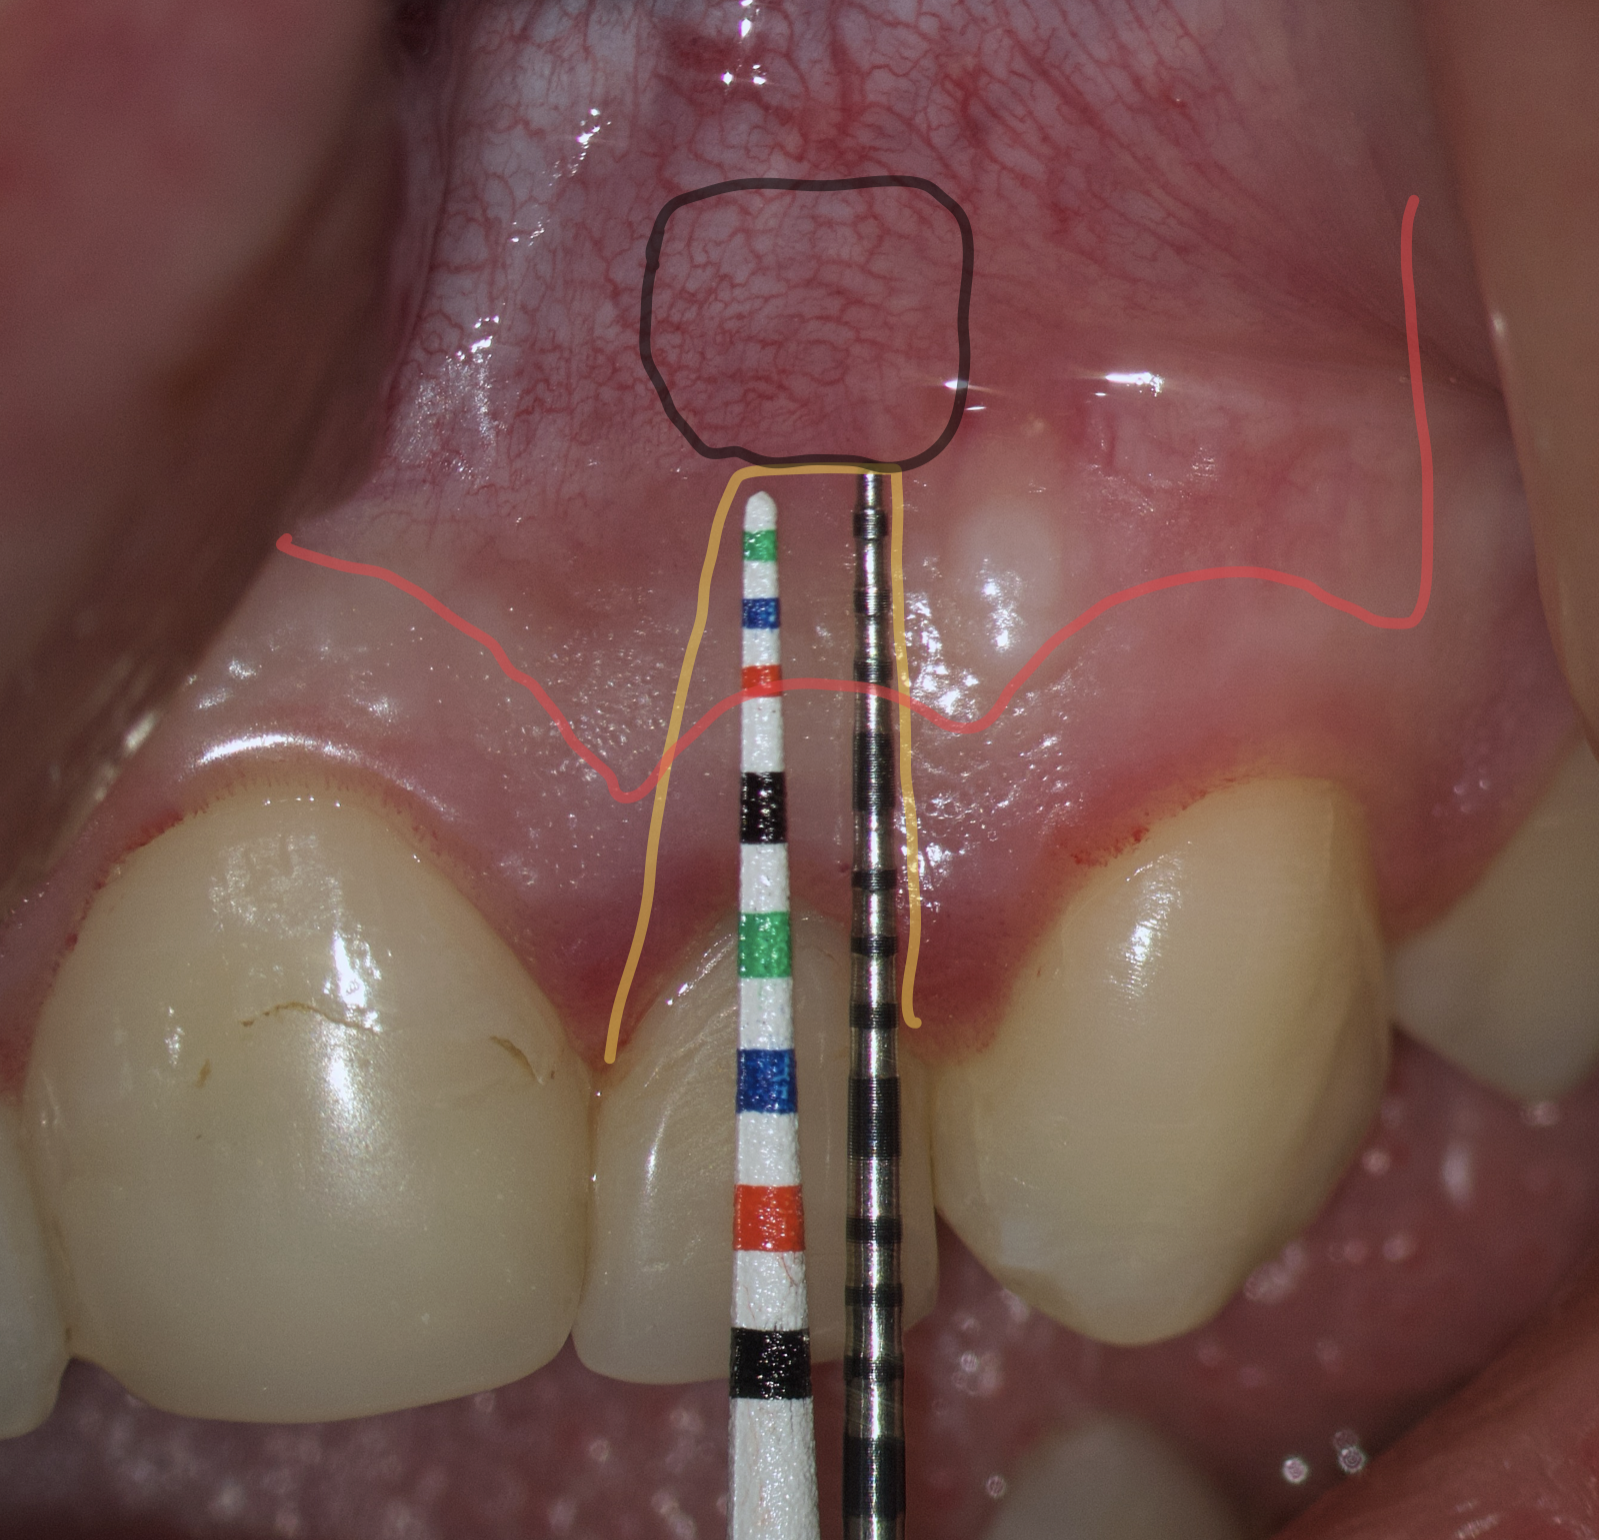

The most popular paramarginal or submarginal flap is the one designed by Clifford Ochsenbein and Raymond G. Luebke (1974) [4, 5]. The Ochsenbein-Luebke flap is formed by a scalloped horizontal sub-marginal incision placed within the attached gingiva, which follows roughly parallel to the contour of the gingival margin. The horizontal incision continues with two vertical releasing incisions [6]. These vertical incisions extend from a point 1 to 2 mm short of entering the mucobuccal fold to a point on the attached gingiva approximately 3 to 5 mm above or below the marginal gingiva and the sulcus depth (Figs 1 and 2) [7, 8].

The submarginal flap is only to be used, when there is a broad zone of attached gingiva with a minimum of 2 mm [9]. The width of the attached gingiva is then calculated on the basis of the distance from the base of the sulcus to the linea girlandiformis (mucogingival junction) [6]. Consequently, the incision must be placed at least 2 mm from the depth of the gingival sulcus. Extensive periodontal probing should be done to establish the depth of the gingival sulcus before the incision is made [10]. Periodontal probing should be conducted not only around the causative tooth but also in the adjacent teeth.

Therefore, the selection of this type of incision requires thorough treatment planning [12]. To avoid the incision falling into an existing bone defect or a defect created by an osteotomy, it is rational to plan a submarginal incision. We can determine whether we can make it, according to the clinical situation of a patient by following approach. To do this, first we need to determine on the CBCT where the bone defect is located or where the osteotomy will take place. Then, using a virtual ruler, measure the distance from the incisal edge of the tooth on which the intervention will be performed to the beginning of the bone defect or osteotomy (Fig 7).

We transfer this distance is transferred to a metal probe and fixed with an endodontic stopper. Next, we take a plastic probe and substitute it near the zenith of a tooth on which the intervention will be performed at a mark of 6 mm (3 mm must be retreated to perform a submarginal incision and another 3 mm is needed for the formed flap to overlap healthy bone tissue) (Fig 8).